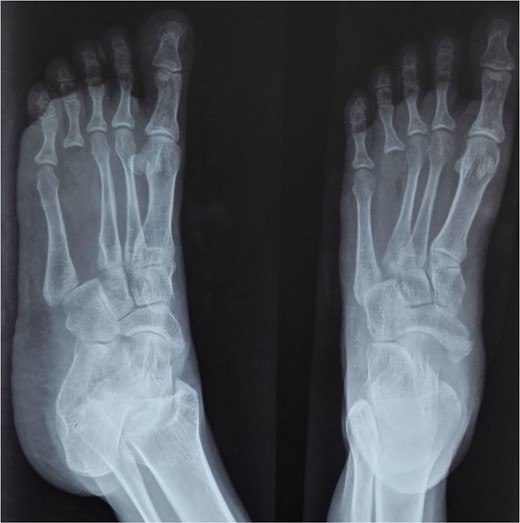

On physical examination, there was a firm, fusiform swelling over the fifth metacarpal without skin changes or tenderness. The range of motion in adjacent joints was preserved. Radiographs revealed a large, expansile lytic lesion in the diaphysis of the fifth metacarpal, with cortical thinning-indicative of recurrent GCT (Fig. 1). A biopsy confirmed the diagnosis.

X-ray of the right hand shows an expansile, lytic lesion in the diaphysis of the fifth metacarpal with a “paper-thin” cortex extending to the subchondral bone.